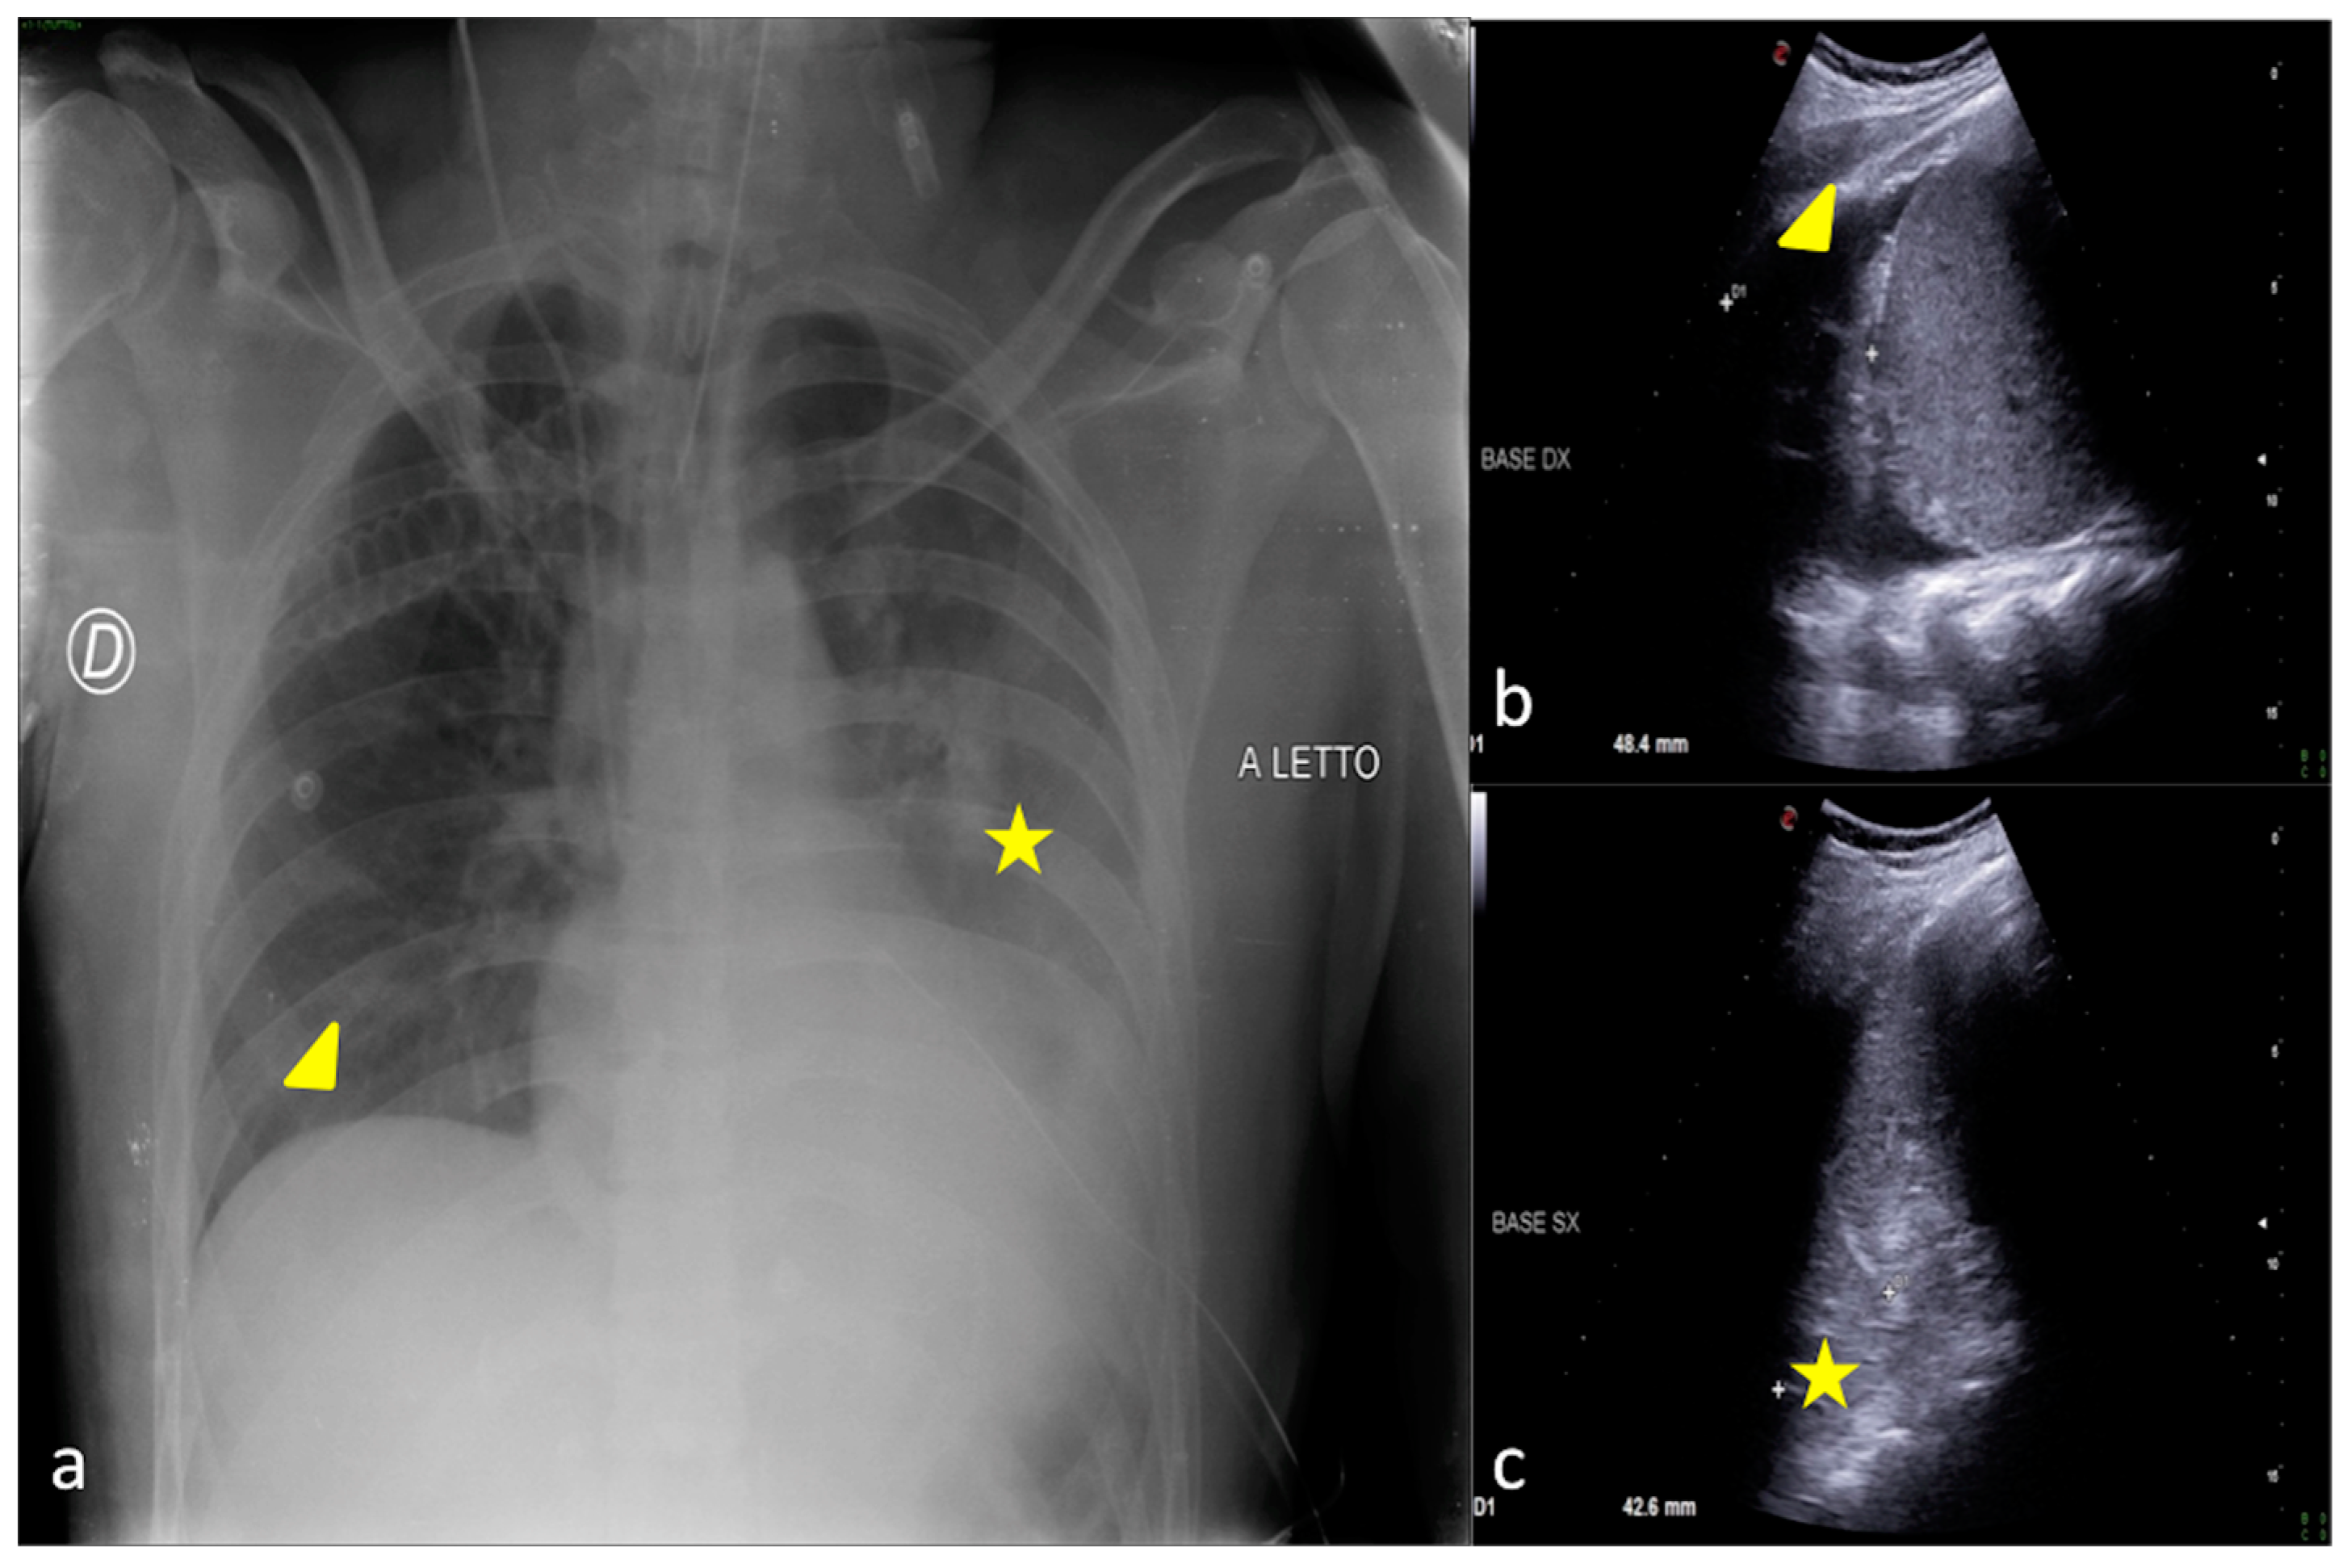

Figure 4.

A 27-year-old male patient admitted to the ICU for high-grade gunshot trauma with abdominal involvement and a clinically worsened condition after intubation. Bedside CXR (a,d) and LUS (b,c). (a) The admission CXR showed a good expansion of the lungs with just a subtle and blurred opacity in the left inferior field (arrow). (b,c) LUS follow-up was performed after 2 days with evidence of hypoechogenic consolidative change in the left parenchyma (b, star) and a compact disposition of the B-lines as a sign of interstitial involvement (c, arrowhead) suggestive of phlogistic parenchymal complication. (d) The CXR confirmed the LUS findings showing some ovular opacity with a confluence trend occupying the left superior, middle, and inferior pulmonary fields (d, arrows).